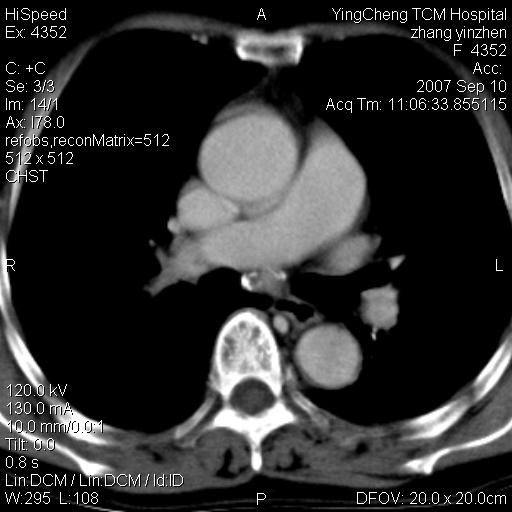

以下是引用夏季在2007-9-18 11:00:00的发言:[br]1。右肺肿块,周围有短毛刺,肺门侧有血管与其相连,胸壁侧有胸膜凹陷征,考虑周围性肺癌 2。左侧甲状腺软组织肿块,内有高密度钙化灶,考虑左侧甲状腺腺瘤。

以下是引用卜一在2007-9-18 14:41:00的发言:[br]右肺肿块:毛刺+胸膜凹陷征+供血血管+浅分叶+强化。支持:周围性肺癌 !另:左侧甲状腺腺瘤!